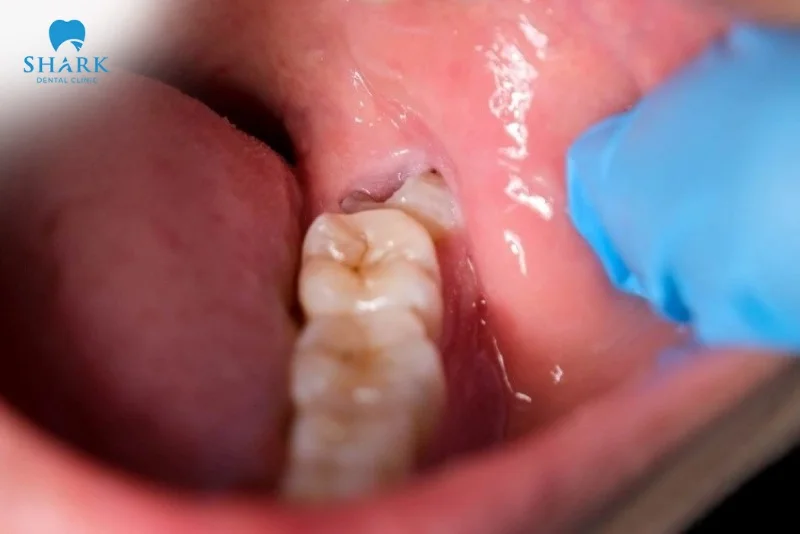

So với răng khôn hàm trên, răng khôn hàm dưới thường đau hơn do xương hàm dưới cứng và ít khoảng trống, khiến răng khó mọc thẳng. Điều này dễ dẫn đến các tình trạng như răng khôn mọc lệch, mọc ngầm, mọc nghiêng, gây đau nhức kéo dài. Ngoài ra, vị trí sâu và khó vệ sinh còn làm tăng nguy cơ viêm lợi trùm, sưng nướu răng khôn, sưng má, khó há miệng, thậm chí đau lan lên tai hoặc thái dương do ảnh hưởng dây thần kinh hàm dưới.

Đặc biệt, nếu hàm dưới răng khôn mọc lệch hoặc răng khôn mọc ngầm, các triệu chứng sẽ nặng hơn nhiều như sưng má rõ rệt, đau kéo dài, khó há miệng hoặc thậm chí viêm nhiễm tái phát. Đây là dấu hiệu cho thấy bạn cần thăm khám nha sĩ sớm để được đánh giá và xử lý an toàn.